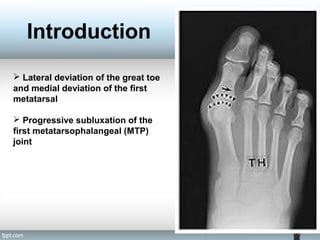

 Lateral deviation of the great toe

and medial deviation of the first

metatarsal

 Progressive subluxation of the

first metatarsophalangeal (MTP)

joint

 Lateral deviationof the great toe and medial deviation of the first metatarsal  Progressive subluxation of the first metatarsophalangeal (MTP) joint Introduction